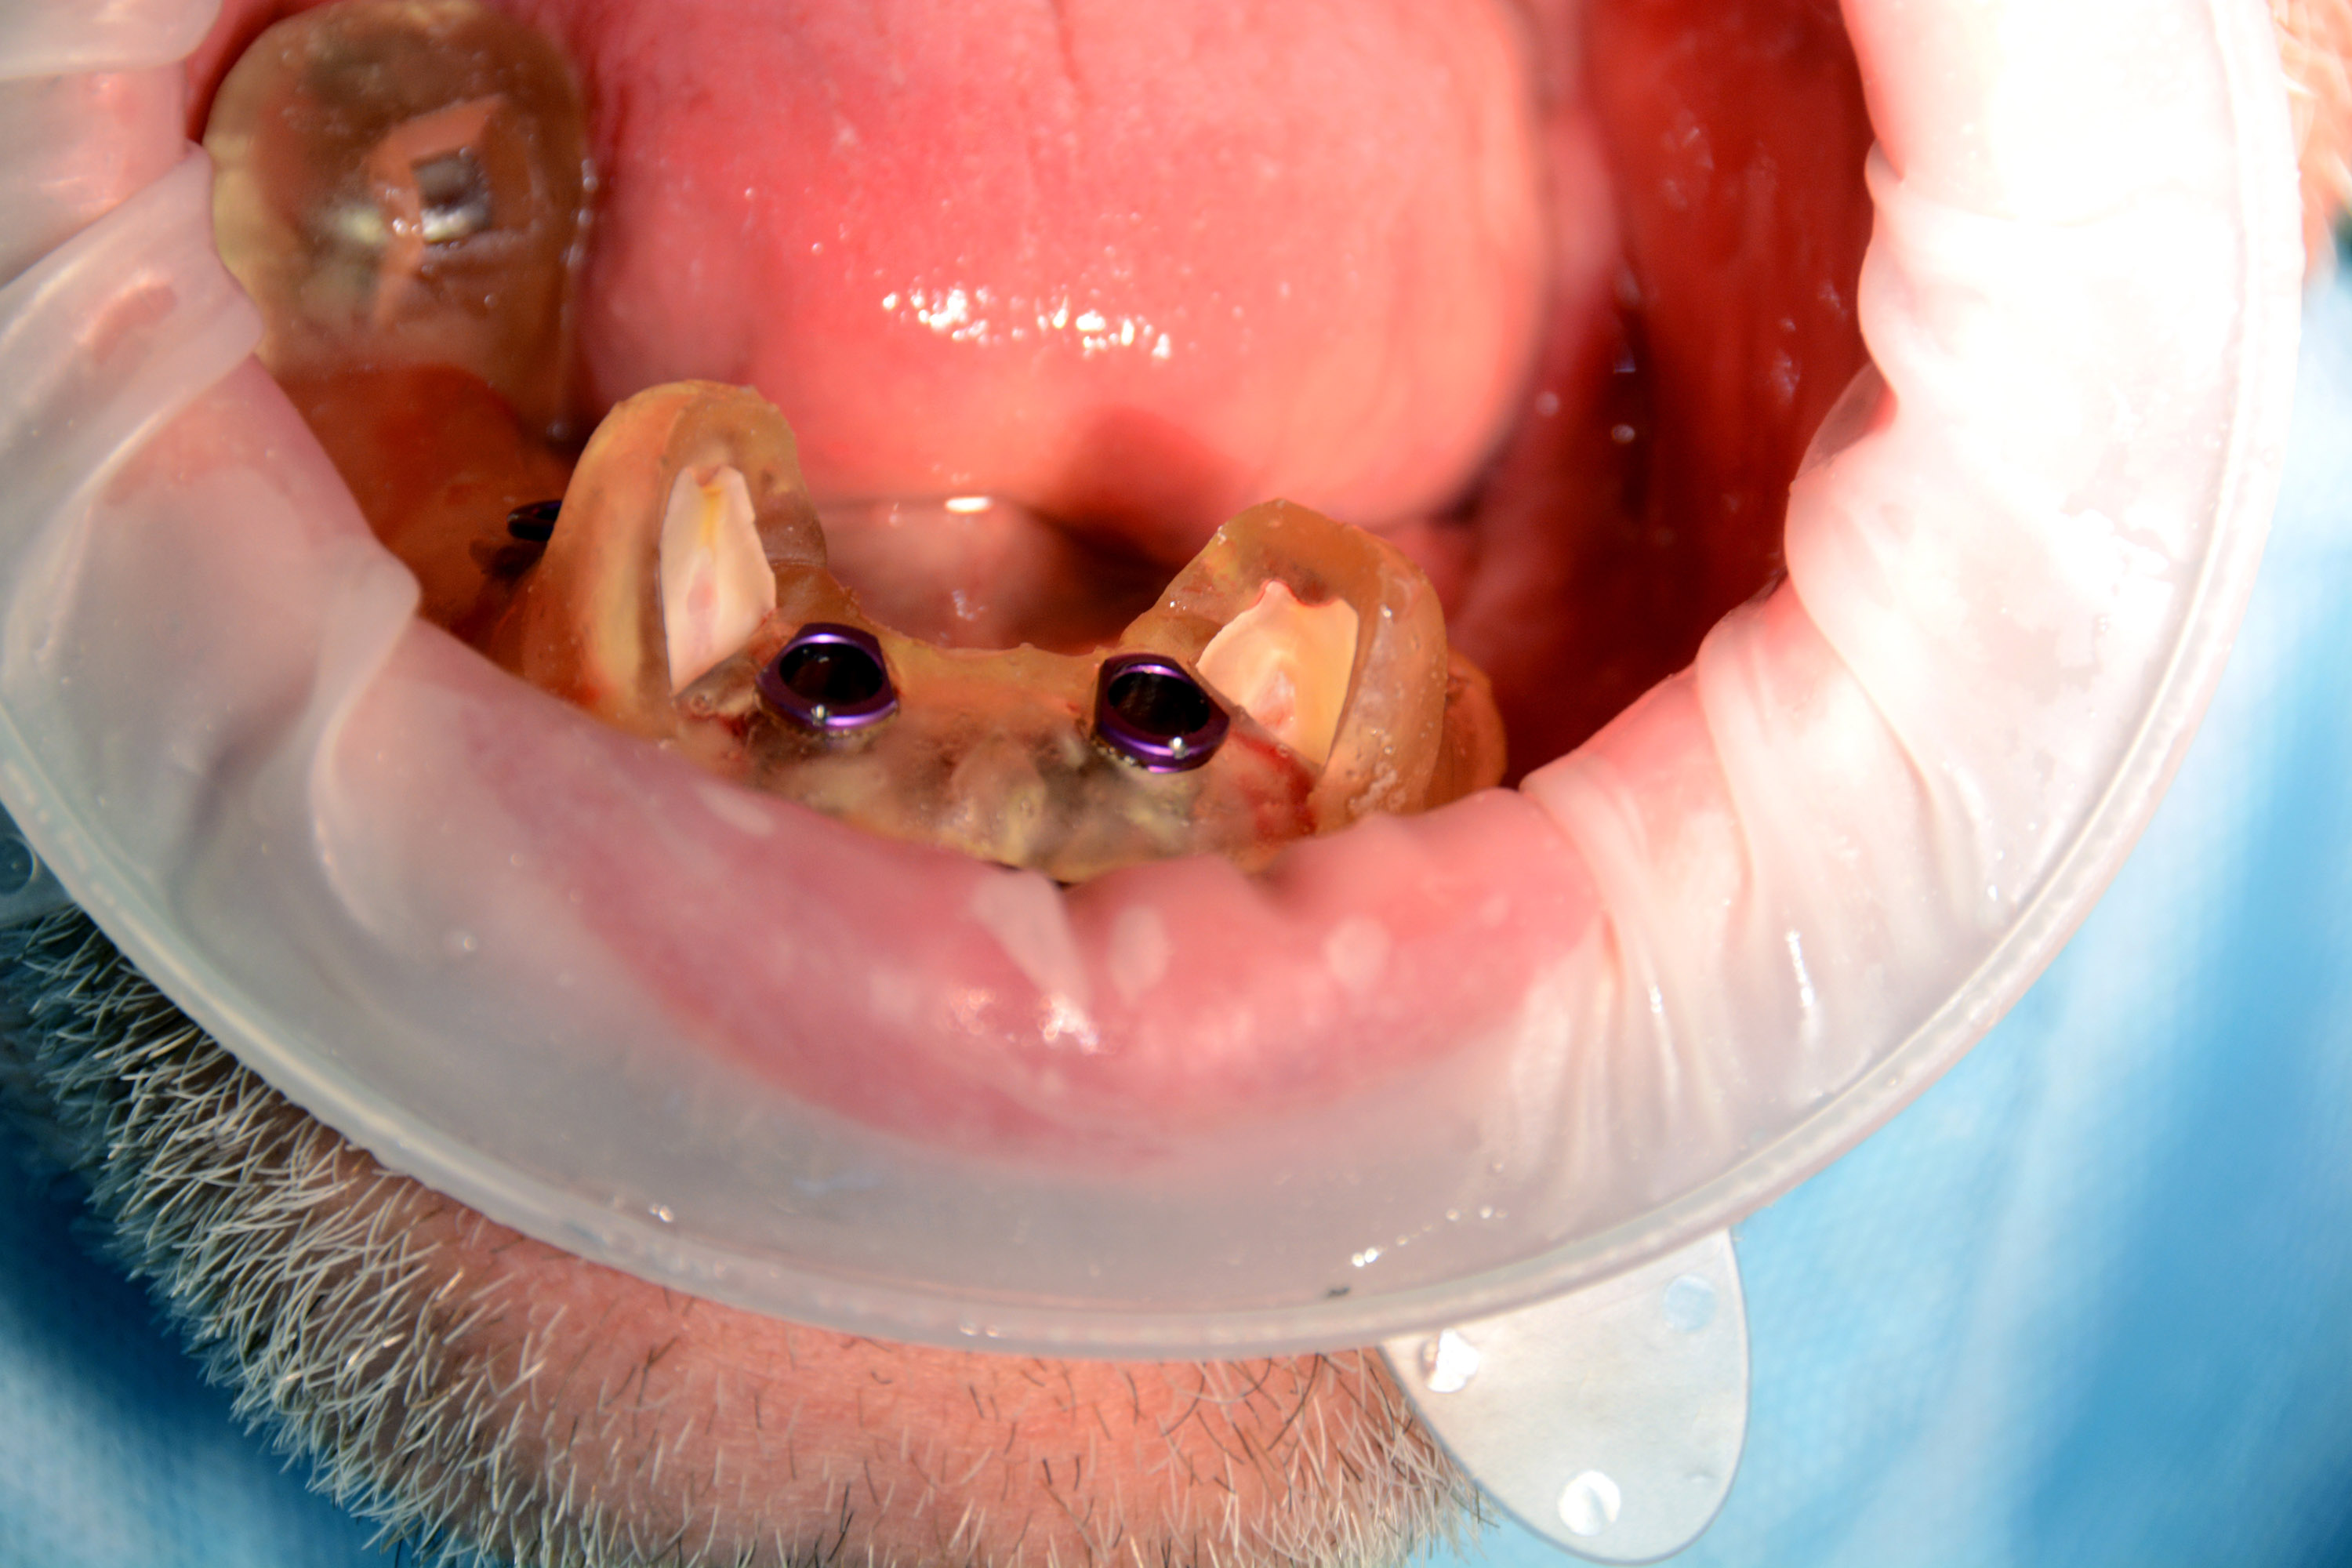

Następnie kursanci pod kierunkiem Dyrektora Naukowego Instytutu Vivadental Dr n. med. Violetty Szycik oraz Mentora Sesji Dr n. med. Adama Nowickiego czynnie uczestniczyli w dwóch złożonych zabiegach z wykorzystaniem pełnej nawigacji chirurgicznej.

Pierwszy zabieg polegał na usunięciu 6 zębów w żuchwie i wprowadzeniu 4 implantów z wykorzystaniem szablonu chirurgicznego do pełnej nawigacji. Bezpośrednio po zabiegu zostały przykręcone multiunity do implantów i osadzony tymczasowy most.